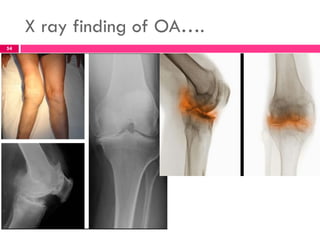

SURGICAL MANAGEMENT

 In moderate to severe OA, when pain is severe or

because of loss of function, surgical intervention

may be used.

 Procedures most commonly used are:

 Osteotomy- to alter the force distribution in the

joint and

 Arthroplasty- diseased joint components are

replaced with artificial products.